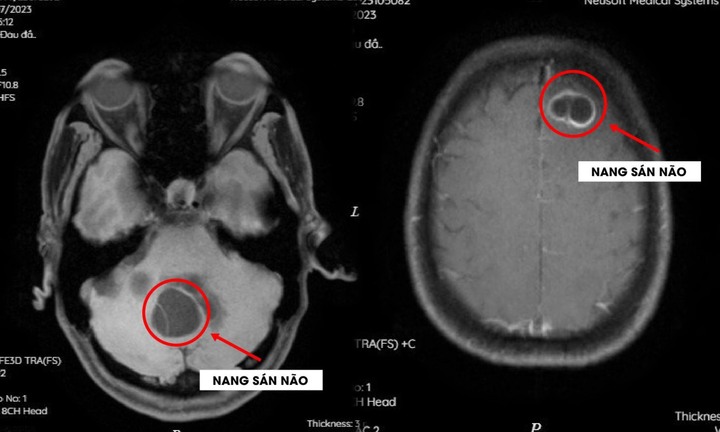

Sán làm tổ trong não do thói quen ăn tiết canh

Hai bệnh nhân nam nhập viện được chẩn đoán sán não do thói quen ăn tiết canh.